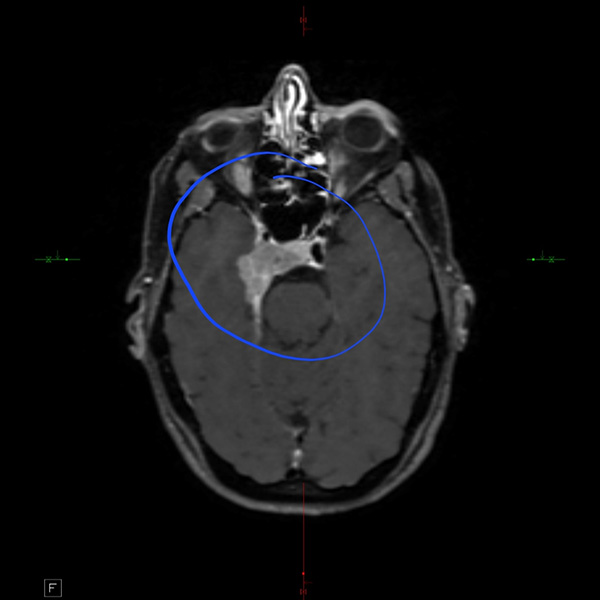

An MRI scan of a brain shows a tumor

Amanda’s scan

The meningioma tumor was located in the cavernous sinus, in the circle of Willis. I had never heard of that either. It’s an area where all of your cranial nerves cross, where your carotid artery is — basically a place full of structures that are vital. Neurosurgeons don’t like to operate there.